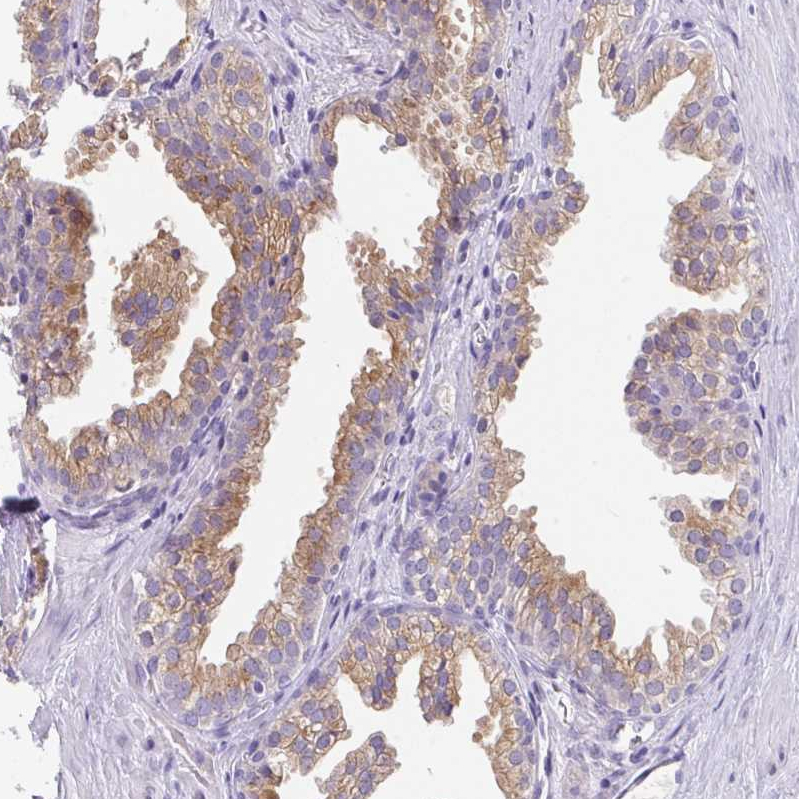

Immunohistochemical staining of human small intestine shows strong cytoplasm granular positivity in glandular cells.